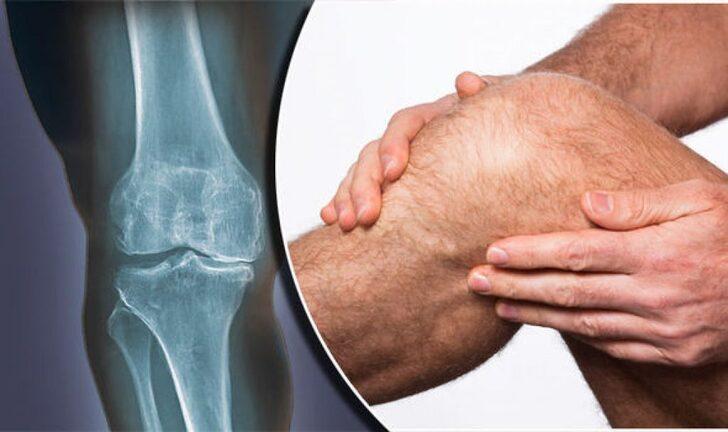

Остеоартроз коленного сустава (гонартроз) - это хроническое прогрессирующее дегенеративно-дистрофическое заболевание сустава, которое характеризуется деструкцией суставного хряща с последующим развитием краевых костных разрастаний, воспалительных и дистрофических изменений в синовиальной оболочке, связочном аппарате и периартикулярных мышцах.

В основе патогенеза лежит нарушение структуры и обменных процессов в хрящевой ткани, что приводит к разрушению хряща и изменениям в других тканях сустава.

Основные симптомы остеоартроза коленного сустава:

• Боль в колене, усиливающаяся при движении

• Хруст и скрип в суставе при движении

• Ограничение подвижности коленного сустава

• Припухлость сустава

Основным методом диагностики остеоартроза коленного сустава является рентгенография, позволяющая определить стадию заболевания.